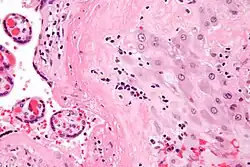

| Micrograph of a chronic deciduitis, showing the characteristic plasma cells. H&E stain. | |

Chronic deciduitis is a type of long-lasting inflammation that arises in pregnancy and affects the endometrial stromal tissue (decidua).

It is associated with preterm labour.[1] The diagnosis rests primarily on the presence of plasma cells.[2]